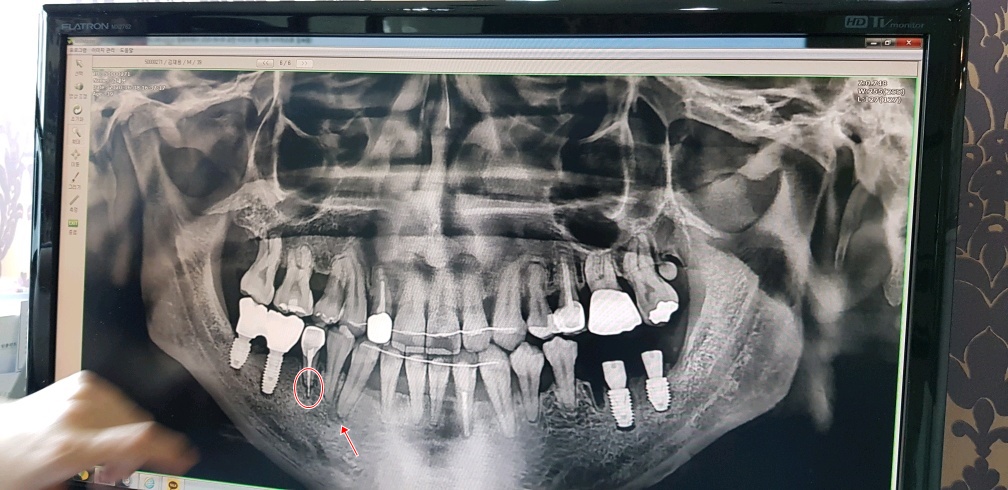

화면상에서 왼쪽치아 두개는 잘 됐다고 해서 다행인데

오른쪽 어금니 치아 두개다가 상태가 영...심각하다..

여기 원장님 말로는 엑스레이 보여주면서

다른 교정치과에서 치료했던 치아가 문제인것 같다 한다..

신경치료 하면서 심어놨던 하얀색(치아뿌리의 중간부분)이 치아뿌리 안쪽에만 있어야 되는데

뿌리를 넘어서서 아픈것일 수도 있다고 하고(실제로 살짝 딱딱한걸 깨물어 보면 통증이 장난아니다..)

두번째로는 화살표 표시해둔 부분 이부분이 치아뿌리 끝 부터 염증이 생겨서 아픈것 일수도 있다고 한다..

우선 임플란트수술 하고 집에 오긴 했으나 수술한 곳은 안아픈데 동그란표시해 둔 저 치아가 너무 아파서

몇시간 마다 진통제 없이는 못버틸 정도로 아프다...